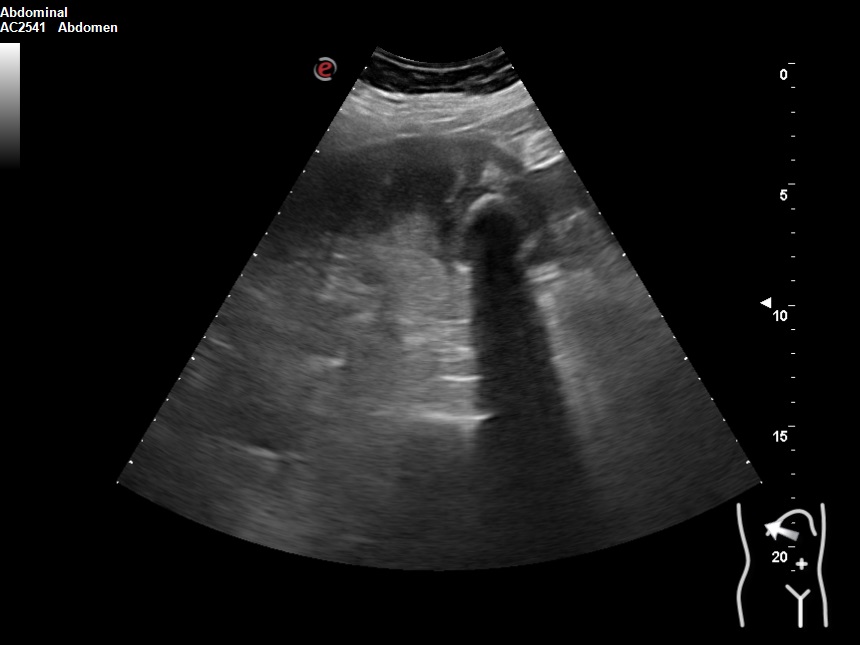

Hallazgos ecográficos

Vesícula biliar desestructurada, de paredes mal definidas con litiasis de 20 mm, que contacta con la pared de la segunda porción duodenal. Porta de tamaño normal. Vía biliar no dilatada.

Juicio clínico: Colecistitis sobre colecistopatía crónica planteando

Diagnóstico diferencial con: pancreatitis, no encajaría con la ictericia y los hallazgos ecográficos; colédocolitiasis, compatible con la ictericia; neoplasia, estaría en contra lo agudo del cuadro.